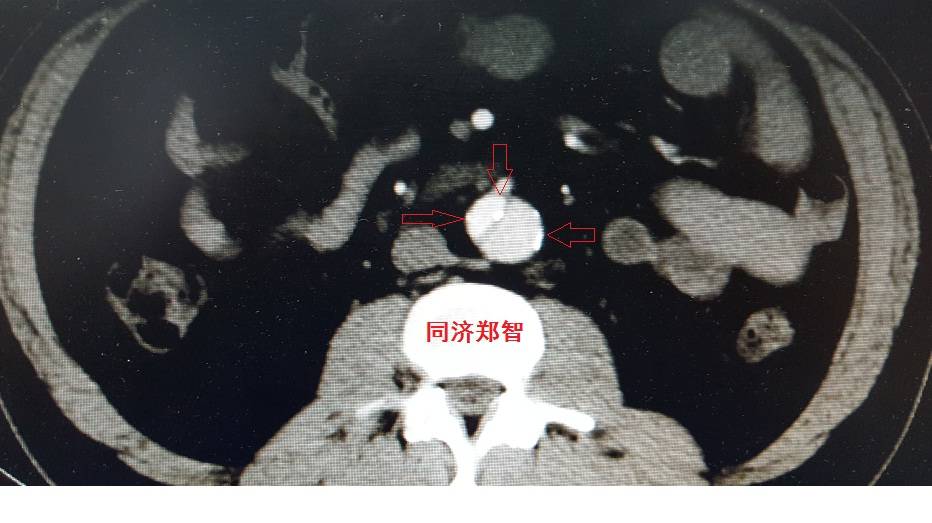

病例四

腹部平扫CT提示腹主动脉增宽,CTA证实为腹主动脉局限性夹层(红箭头所示)